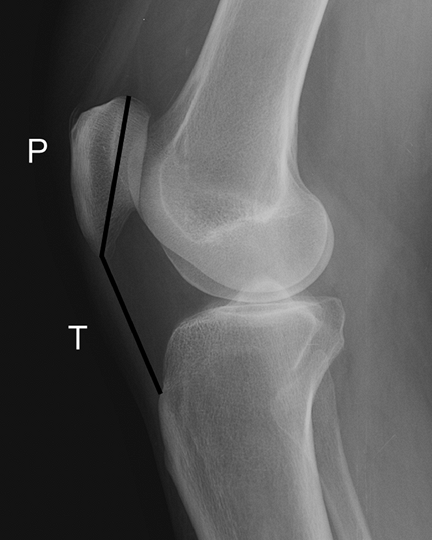

Figure 17-2

Lateral view of the knee. The Insall-Salvati ratio (T/P) can be used to determine the height of the patella relative to the sulcus of the distal femur. The ratio of the length of the patellar tendon (T) to the diagonal length of the patella (P) should differ by no more than 20%. |

be evaluated on both the lateral and axial images of the knee. The

lateral radiograph using the Insall-Salvati ratio (Fig. 17-2).

Normal patellar height is represented by a ratio of one, whereas ratios

of 0.8 and 1.2 represent patella baja and patella alta, respectively.